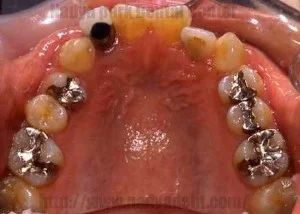

Before

After

古い金属の詰め物をすべて除去し、セラミック等の白い材料でやりかえた事例

噛み合わせの調整後、金属除去、型採り、装着のステップで実施 / セラミック1本 ¥80,000~(税別) + 型取り ¥3,000(税別) (※本症例では右下6・左下6にセラミック、右下7・左下7に保険内CR、その他小金属に保険内修復を適用)リスク・副作用:治療後に一時的なしみや違和感が生じる可能性。過度な衝撃による破損や、経年劣化による変色・脱離のリスク。